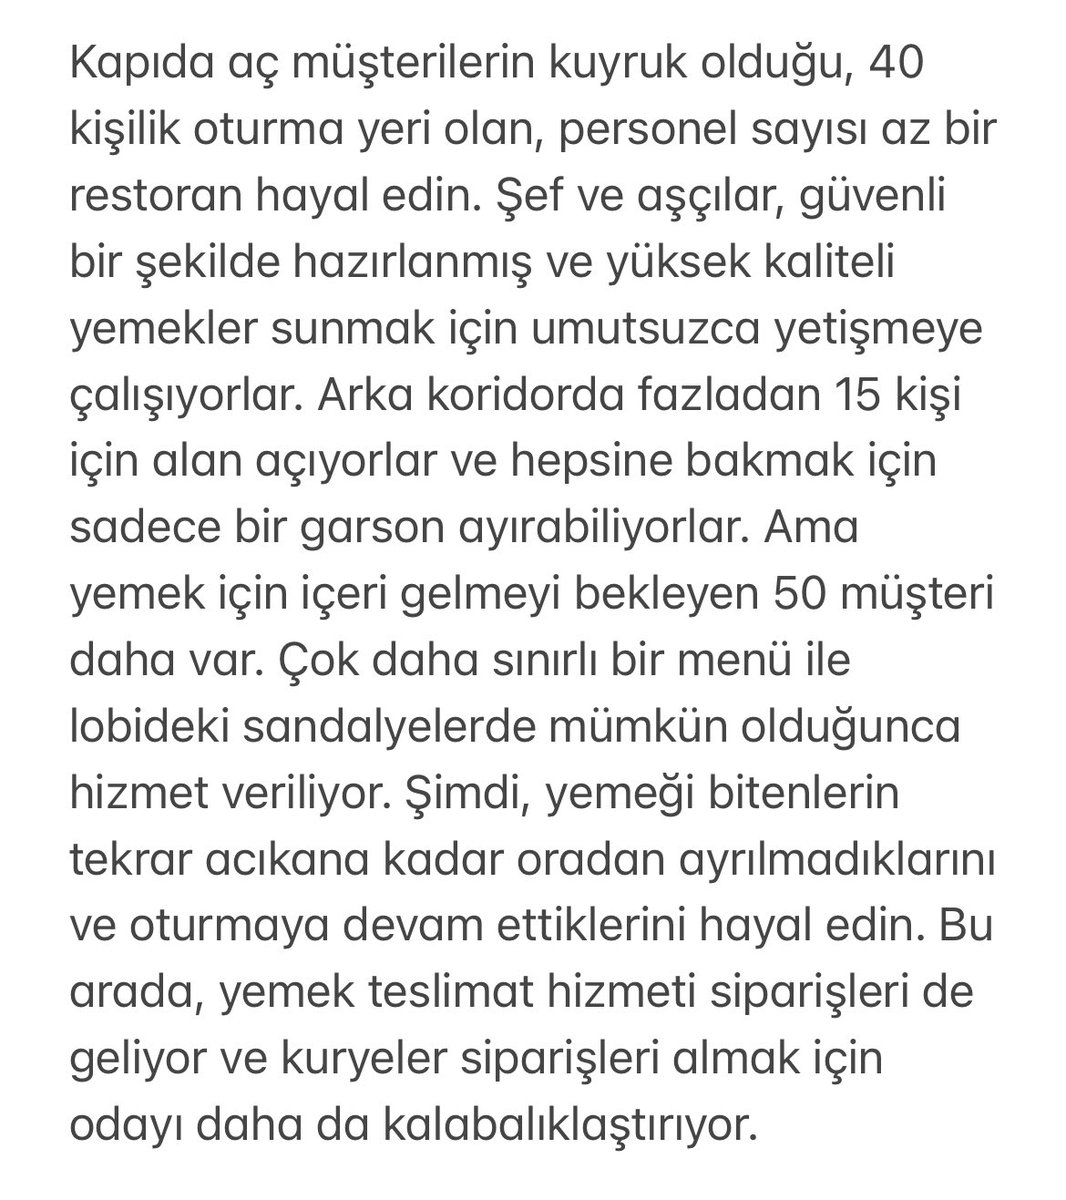

Acile yer açmak lazım ! #AcillerFazlaYükAltında #AcillerAşırıKalabalık #NoMoreLivesLostWaiting #ResetEmergencyCare International Federation for Emergency Medicine Türkiye Acil Tıp Derneği - TATD (EMAT)